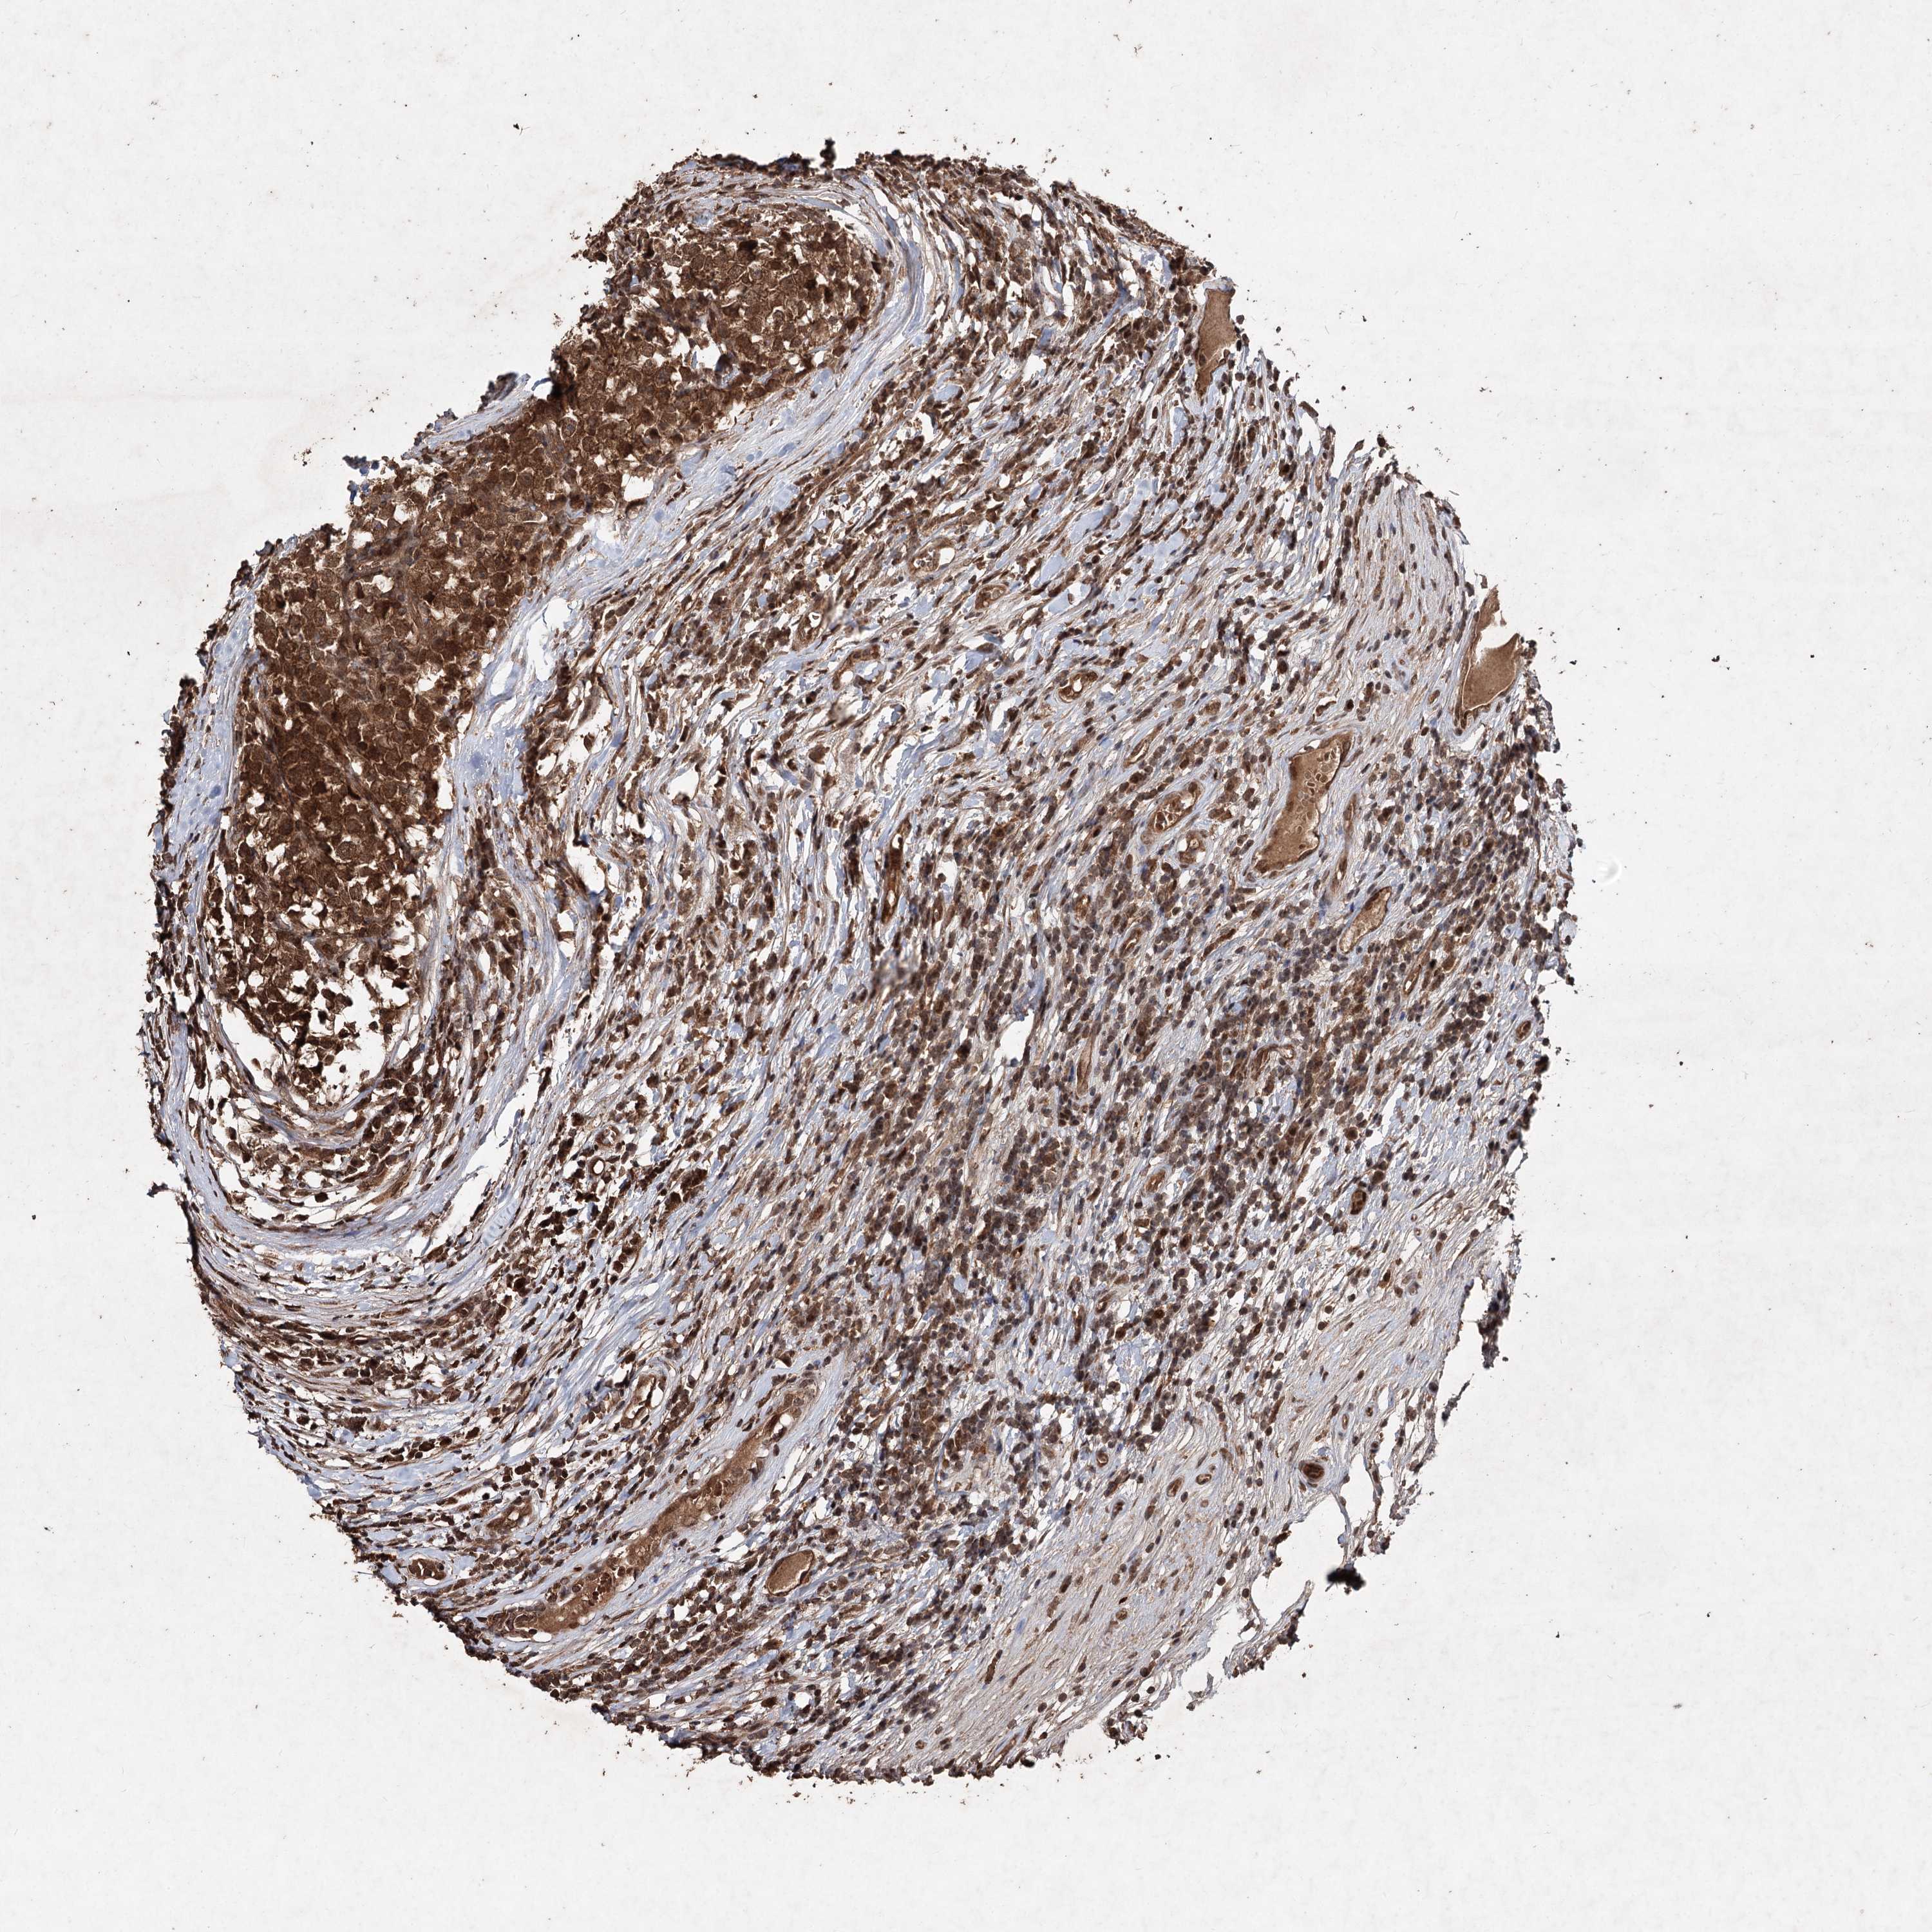

TESTIS CANCER - Protein expressioni

A mouse-over function shows sample information and annotation data. Click on an image to view it in a full screen mode. Samples can be filtered based on level of antibody staining by selecting one or several of the following categories: high, medium, low and not detected. The assay and annotation is described here.

Note that samples used for immunohistochemistry by the Human Protein Atlas do not correspond to samples in the TCGA dataset.

Antibody stainingi

Antibody staining in the annotated cell types in the current human tissue is reported as not detected, low, medium, or high, based on conventional immunohistochemistry profiling in selected tissues. This score is based on the combination of the staining intensity and fraction of stained cells.

Each image is clickable and will lead to virtual microscopy that enables deeper exploration of all samples and also displays staining intensity scores, fraction scores and subcellular localization as well as patient and tissue information for each sample.

Antibody HPA032114

Antibody HPA057352

Antibody CAB034296

Carcinoma, Embryonal, NOS

Seminoma, NOS

Urothelial carcinoma, High grade